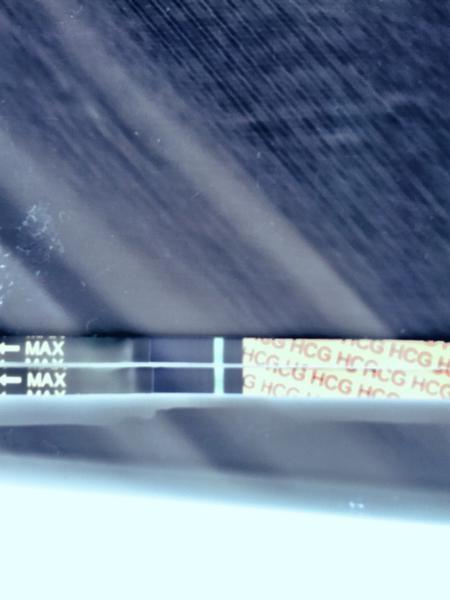

Duch na teste 2

@fire_proof ahoooj... gratulujem... ja som to tušila... keď som ti pred par dňami písala, že na tvojom teste niečo vidím 😊😊😊. Držte sa a moooc moooc držím palce 👍❤👌